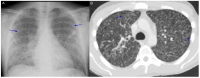

Coccidioidomycosis is a disease caused by soil fungi of the genus Coccidioides, divided genetically into Coccidioides immitis (California isolates) and Coccidioides posadasii (isolates outside California). Coccidioidomycosis is transmitted through the inhalation of fungal spores, arthroconidia, which can cause disease in susceptible mammalian hosts, including humans. Coccidioidomycosis is endemic to the western part of the United States of America, including the central valley of California, Arizona, New Mexico, and parts of western Texas. Cases have been reported in other regions in different states, and endemic pockets are present in these states. The incidence of reported cases of coccidioidomycosis has notably increased since it became reportable in 1995. Clinically, the infection ranges from asymptomatic to fatal disease due to pneumonia or disseminated states. The recognition of coccidioidomycosis can be challenging, as it frequently mimics bacterial community-acquired pneumonia. The diagnosis of coccidioidomycosis is frequently dependent on serologic testing, the results of which can take several days or longer to obtain. Coccidioidomycosis continues to present challenges for clinicians, and suspected cases can be easily missed. The challenges of coccidioidomycosis disease, from presentation to diagnosis to treatment, remain a hurdle for clinicians, and further research is needed to address these challenges.

Keywords: coccidioidomycosis; lung mass; pulmonary nodules; pyopneumothorax; valley fever.